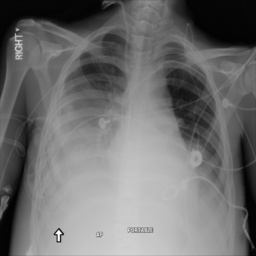

Figure 2: Examples of normal vs. abnormal images of considered datasets. Natural images: (first row) cars vs other classes of CIFAR10 dataset [1], (second row) digits “0” vs digits “1” – “9” of SVHN dataset [2]. Medical images: (third row) healthy tissue vs. tissue with metastases in H&E-stained lymph nodes images from Camelyon16 challenge [3], (fourth row) normal chest X-rays vs. chest X-rays with abnormal findings from NIH dataset [4].

Anomaly detection is a crucial task in the deployment of machine learning models, where knowing the “normal” data samples should help spot the “abnormal” ones [5, 6]. If an input deviates from the training data substantially (e.g., the input belongs to a class not represented in the training data), it is usually impossible to predict how the model will behave [7, 8]. This trait is especially important in high-consequence applications, such as medical decision support systems, where it is especially vital to know how to recognize the anomalous data. Identification of rare occurrences is another important application where anomaly detection is useful. For example, in pathology, where labeling diverse microscopy datasets is both time-consuming and expensive, the rare types of cells and tissues require specialized expertise from the annotator [9, 10]. Forthright anomaly classification and segmentation algorithms are typically prone to mistakes either because of the lack of sufficient annotation (thousands of labeled examples needed for supervised models) or because of the lack of representative data altogether (e.g., the case of some rare pathologies). Moreover, these algorithms are affected by the need to deal with very unbalanced and apriori noisy data, frequently leading to inaccurate results (e.g., the findings on chest x-rays can be so subtle that they can lead to disagreement in the interpretation [11, 12]). Because the normal cases greatly prevail over the abnormal ones, the anomaly detection could alleviate the annotation burden by automatically pointing to the rare samples.

In recent years, deep learning techniques achieved important advances in image anomaly detection [13, 14, 15, 16, 17, 18, 19, 20, 21]. However, these efforts were primarily focused on artificial problems with distinct anomalies in natural images (e.g., outliers in images of “cars” in the CIFAR10 dataset [1], see Figure 2). The medical anomalies, however, differ from those in the natural images [15, 19, 22]. Contrary to the natural images, the anomalies in the medical domain tend to strongly resemble the normal data. For example, detection of obscure neoplasms in chest X-rays [4] and of metastases in H&E-stained lymph node images [3] manifest a blatant challenge at hand, with the anomalous tissues being barely different from the normal ones (see Figure 2). Although deep learning has proved useful for a variety of biomedical tasks [23, 24, 25, 26], only recently, a few groups started dedicating their effort to the anomaly detection problem [15, 19, 27]. However, to the best of our knowledge, a thorough comparison of the state-of-the-art (SOTA) solutions in the medical domain is still missing despite the pressing demand and the prospective clinical value.

Anomaly Detection on Chest X-Rays

Chest X-ray is one of the most common examinations for diagnosing various lung diseases. We considered the task of the recognition of fourteen findings, such as Atelectasis or Cardiomegaly, on the chest X-rays in the NIH dataset (ChestX-ray14 dataset) [4] (Figure 2). Searching abnormalities on a chest x-ray is challenging even for an experienced radiologist since abnormality may occupy only a small region of lungs, or be almost invisible. The dataset consists of 112,120 frontal-view images of 30,805 unique patients: 86523 for training, 25595 for evaluation. We split the dataset into two sub-datasets having only posteroanterior (PA) or anteroposterior (AP) projections, because organs on them look differently. We tried different preprocessing during the hyperparameter search: rescaling to 256x256, 128x128, and 64x64 and histogram equalization, central crop (3/4 of the image size) to delete “noisy” borders. We considered images without any disease marker as “normal” and used them for training. Abnormal images for hyperparameter searching comprised of the training images of the most frequent disease (‘Infiltration’) out of fourteen possibilities. We also evaluated model on subset containing “clearer” normal/abnormal cases (provided by  [22]). This subset consists of 4261 normal images for training, 849 normal and 857 abnormal images for validation, and 677 normal and 677 abnormal images for testing.

Figure 6: Examples of normal (left) and anomaly (right) images of H&E-stained lymph node of Camelyon16 challenge [3] (top) and chest X-rays of NIH dataset [4] (bottom). We also showed the predicted anomaly score by the proposed method. The higher the score, the more likely to be an anomaly. Notice how the proposed method spots even the borderline cases.